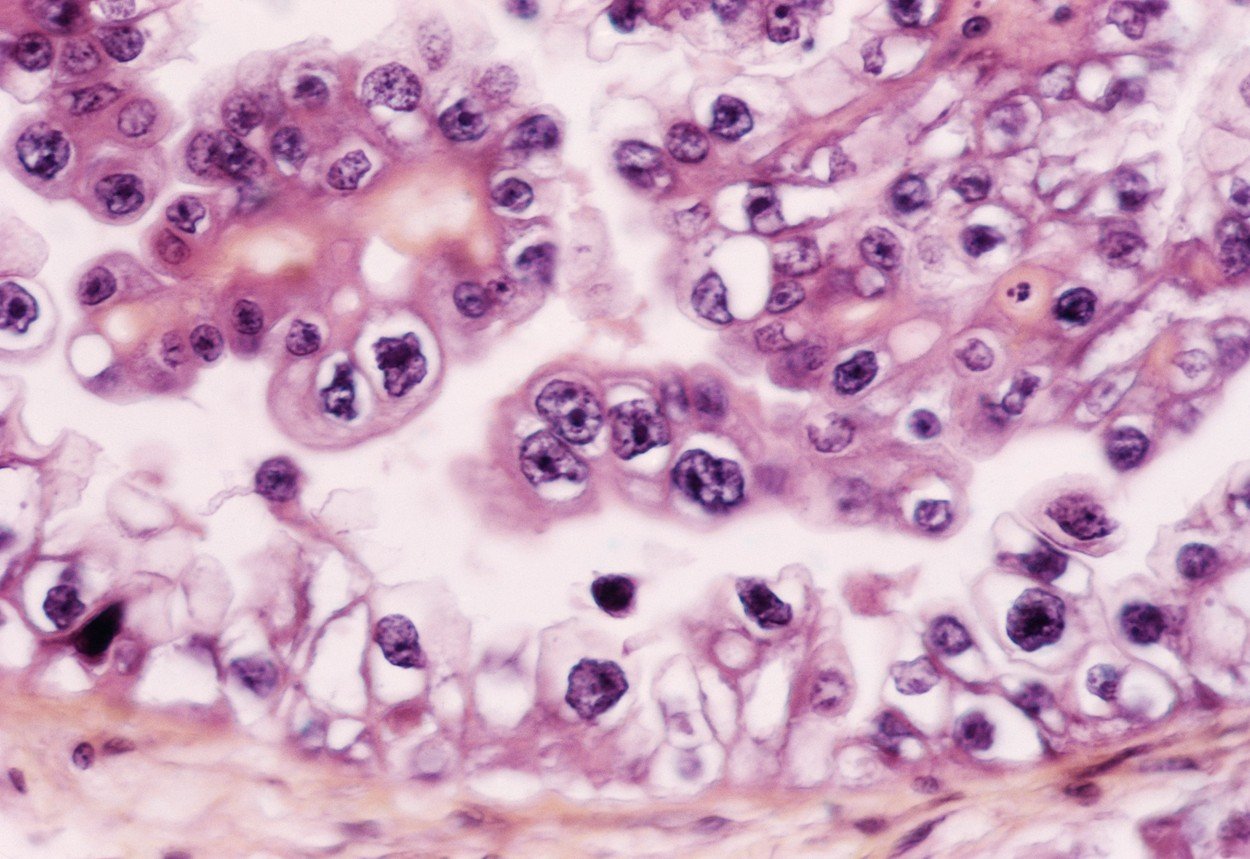

Krvna pretraga za 10 različitih vrsta raka mogla bi jednog dana pomagati liječnicima da utvrde bolest prije nego što pacijenti pokažu simptome, piše Guardian.

Naime, pretraga pod nazivom likvidna biopsija detektira sićušne dijelove DNK koje u krv ispuštaju stanice raka. Naročito dobre rezultate pretraga daje u slučaju raka jajnika i gušterače, iako se radi o malom broju detektiranih rakova do sada (putem ove metode ukupno je utvrđeno tek 10 slučajeva raka jajnika, iako je čak 90% pouzdan način).